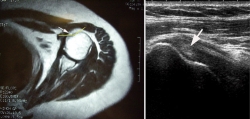

Figura 2. A: resonancia magnética (RM) del hombro afecto. Se aprecia aumento del ángulo de la corredera bicipital y ausencia del tendón de la porción larga del bíceps; B: ecografía del hombro derecho (contralateral). Se observa ausencia de la porción larga del músculo bíceps braquial e hipoplasia de la corredera bicipital (flecha).